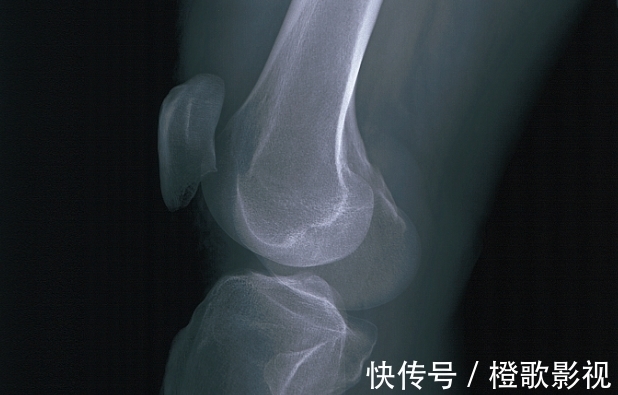

而且陈女士发现,自从生完二宝之后,自己经常腰酸背痛、手脚抽筋,去医院做了检查,医生说可能是骨质疏松引起的,但是陈女士补充了很多钙片,这种情况都没有缓解。

更惨的是,有一天陈女士在下楼梯的时候,不小心踩空摔了下去,结果就造成了严重的骨折,在轮椅上躺了几个月,孩子也只能找保姆来照顾。

其实陈女士的骨头之所以那么脆弱,跟她产后的饮食有很大的关系。